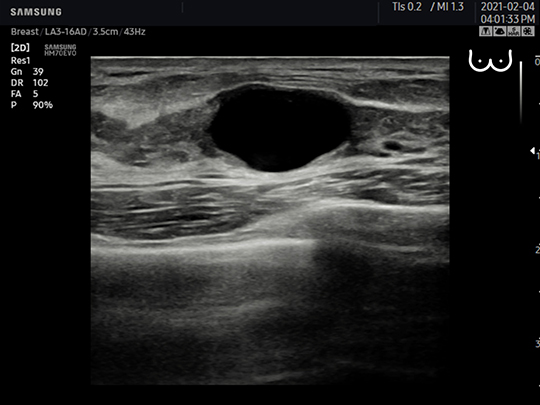

LA3-16AD

- Application: small parts, vascular, musculoskeletal, abdomen, obstetrics, gynecology, pediatric